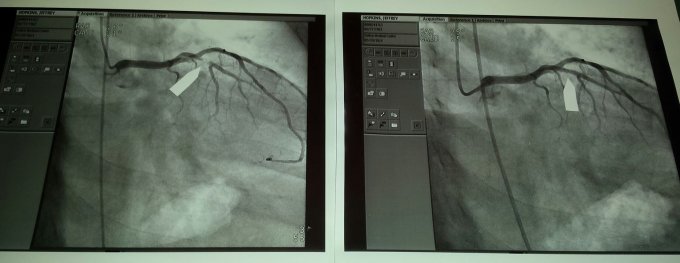

a normal Wednesday a week ago May 28th. Was anything but normal. Got up and had coffee as usual, watch a little news I noticed a slight feeling of like a pectoral muscle starting to pull. Didnt think too much about it. Off to the shower as I had a Dr appt for my total knee replacement. Getting dressed and heading down stairs the pain was getting worse and moving into my left arm. Not feeling well at all, I told Deener that I think I'm going to stop off at the E.R. before my appt. She took on look at me and said "your not driving" and off we went ( should have called 911) At the E.R. I told them I thought I was having a heart attack. Great people there. They got me right in and the next thing I knew I was hooked up to an I.V. had 3 nitro taps and 2 shots of morphine in less then 20 minutes. ultra sound on my legs looking for blood clots, nucular lung tests and yip i was having a Heart attack. Do to being a little dehydrated I needed fluid befor they could work on me. The pain had gone way, Great drugs there. 7:45am Thursday I had a stint put in an aterie that was 99% blocked. That was very painful to say the least. Everything went well. I was discharged on Friday late morning. Doc said on the heart attack scale it was around a 3. Also I was very lucky, The aterie is know as the widow maker. If it had closed 1% more there would have been nothing they could have done. He also said that it looks like very little if any damage was donr to my heart. Wow what an expience that was. Doc wanted me to stay of the bike for a week. See ya at the Redwood Run.....